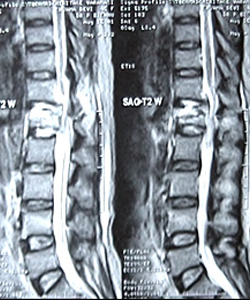

TL Spine Injury Reconstruction Using Stand Alone Titanium Cage by Medtronic’s Inc